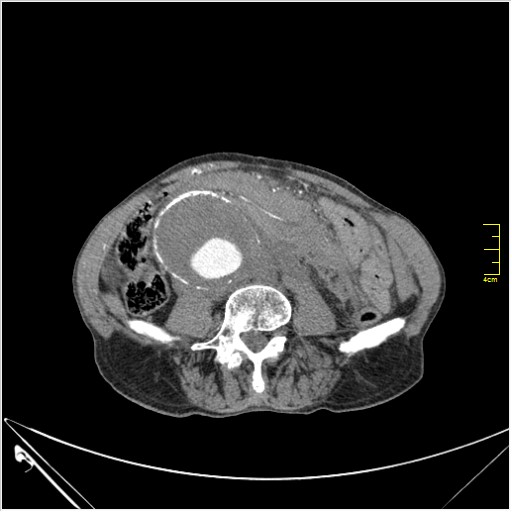

КТ брюшной полости. Мужчина с пальпируемой опухолью в животе

Пациент Т. 64 года, обратился на КТ брюшной полости амбулаторно (!), по направлению семейного врача с диагнозом abdominal mass, буквально: образование брюшной полости.

Uzgraph писал(а):Случай интересный - ногу сломишь. Вроде бы анефризма брюшной аорты(особенно по УЗИ), но что тогда за образования сидят на левой почке - онкология?

ИМХО простые кисты.